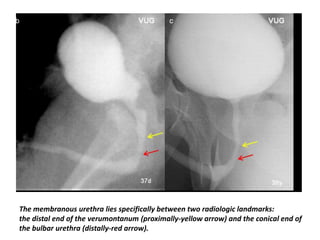

The membranous urethra lies specifically between two radiologic landmarks:

the distal end of the verumontanum (proximally-yellow arrow) and the conical end of

the bulbar urethra (distally-red arrow).

The membranous urethralies specifically between two radiologic landmarks: the distal end of the verumontanum (proximally-yellow arrow) and the conical end of the bulbar urethra (distally-red arrow).